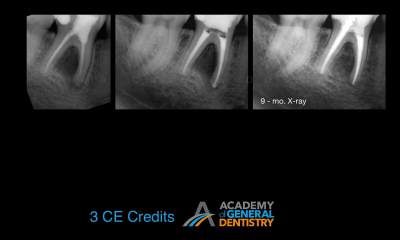

According to literature, the survival rate of endodontically treated teeth is close to 98%. How do we update our understanding of endodontics so that we can care for our patients and close in on the 98% published survival rate? The most common reason for a failed root canal treatment is inadequate treatment. However, there are some cases in which a root canal treatment is carried out in accordance with the highest standards, and yet still results in failure. In most such cases, the endodontic failure results from persistent intra-radicular infection. In other cases, extra-radicular infections and intrinsic or extrinsic non-microbial factors might be implicated in the failure.

The purpose of this lecture is to discuss the etiological factors of failed root canal treatments using a series of clinical cases. It will aid clinicians in choosing between surgical and non-surgical management of a failed root canal in an evidence-based manner. Indications for the non-surgical vs. surgical retreatment of failed endodontic cases are discussed in order to maximize the success of an endodontic retreatment.